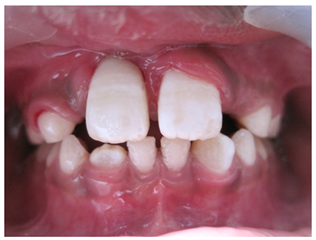

A 10year old boy reported to the department of Pedodontics with a chief complaint of missing upper front tooth and gave a history of fall from bike while 5 days back. They had been to pediatrician for the lacerated lip and got it sutured. Parents had kept the avulsed tooth in paper without knowledge of reimplantation of the same tooth. Patient had no relevant medical and family history. On examination swelling and suture was present on upper lip, lacerated gingiva with healing socket in 11 regions. 21 was intact, vital and non mobile. (Figure 1) (Figure 2) On examination of avulsed tooth 11, it was found to have open apex (Figure 3). On intraoral radiographic examination, no fracture was seen with alveolar bone (Figure 4). Thus avulsed tooth was cleaned and debrided with soft pumice prophylaxis, gentle scaling was done to remove ligament remnants. It was then placed in 1.23% sodium fluoride for 15minutes. Extraoral endodontic therapy was also done using retrograde filling of MTA (Figure 5). Local anesthesia was administered and socket was cleaned, curetted and irrigated to remove clot and debris and 11 was slowly reimplanted in socket. Orthodontic wire – composite splinting was done for 4weeks as the dry storage was more than 60minutes (Figure 6). Systemic antibiotics amoxicillin and doxycycline were prescribed for 5days. The patient was recalled after 1 month and splint was removed. No mobility was present. Again patient was recalled after 2months to check the condition (Figure 7). Again patient was recalled after 6months; tooth had slightly discolored but was not mobile and maintained the space (Figure 8). Patient was happy and contended with the reimplantation of his own tooth without disturbing his original look.

Figure 2 Intraoral pre-operative photograph.